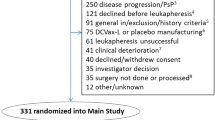

We summarize our experience in a pilot group of eight patients with newly diagnosed GBM treated with immunotherapy (autologous DC loaded with autologous tumor cell lysate) integrated in a standardized fashion in the multimodal standard therapy—surgical resection, radiochemotherapy (RCT), and maintenance temozolomide (TMZm) chemotherapy [1]. The emphasis of this report is on the clinical and immunological feasibility and toxicity of integration of DC vaccination in the conventional therapeutic modalities. The progression free survival data were used to power the currently running phase I/II trial (HGG-2006, EudraCT 2006-003881-20), integrating DC vaccination as an add-on therapy to standard postoperative RCT and maintenance chemotherapy in patients with newly diagnosed GBM.

Patients underwent maximum safe surgical resection of the tumor. Peri-operative corticosteroids were withdrawn within one week after resection. Leukapheresis was performed after histological diagnosis was obtained and inclusion criteria were met (Fig. 1). After leukapheresis, patients were treated with limited field external beam radiotherapy (30 × 2 Gy) and concomitant chemotherapy with TMZ (75 mg/m2) during six weeks as outlined by Stupp et al. [1]. After radiochemotherapy, tumor lysate-loaded DC were injected weekly for four weeks. Following these four weeks, TMZm chemotherapy was started. The maintenance 28-day cycles consisted of five days oral intake of TMZ (150 mg/m2 for the first and 200 mg/m2 for the following cycles). During the first, second, third, and sixth cycles, further boost vaccinations with tumor lysate (without DC) were administered at day 8 of the cycle. At the time of progression possible rescue therapy was at the physician’s discretion.

Treatment schedule. DC-based immunotherapy was integrated in the state-of-the art postoperative radiochemotherapy. Leukapheresis to harvest autologous monocytes is performed once, at least seven days after weaning off steroids and immediately before the start of the concomitant radiochemotherapy. After the radiochemotherapy, but before the maintenance chemotherapy with TMZ, four weekly induction vaccines are administered intradermally to the patient. Afterwards, maintenance chemotherapy (5/28 days) is started and one week after the start of the 1st, 2nd, 3rd, and 6th cycles of TMZ, a boost vaccine is administered